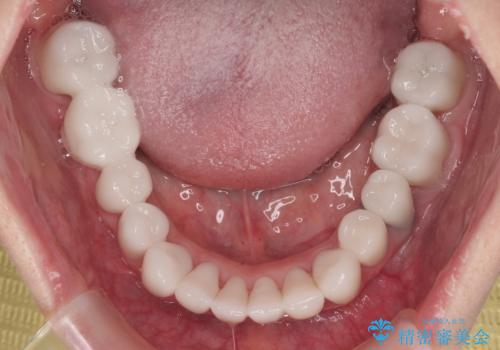

下顎前歯の叢生も気になっており、矯正治療も並行して進めていくこととしました。

多くの外科処置を行ったため、治療期間も長くなり、患者様の負担は非常に大きなものとなりましたが、明るく健康的な口元となり、患者様には大変満足していただけました。